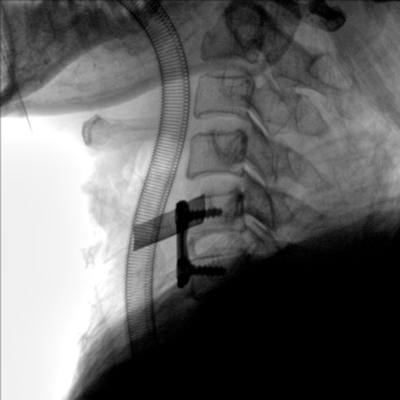

大尺寸動(dòng)態(tài)平板探測(cè)器,高DQE、低噪聲、圖像清晰。采用多分辨率圖像增強(qiáng)處理技術(shù),不同部位不同圖像處理算法,滿足客戶多樣化的需求。

采用智能變頻脈沖透視技術(shù),優(yōu)化圖像質(zhì)量的同時(shí)降低輻射劑量,呵護(hù)醫(yī)患健康

圖形化操控界面設(shè)計(jì):設(shè)有多種人體特征攝影參數(shù),操作簡(jiǎn)便。雙向紅光十字定位系統(tǒng):實(shí)現(xiàn)無射線下的高效定位。信息共享:遵循DICOM3.0格式接口,可無縫對(duì)接云PACS系統(tǒng)。